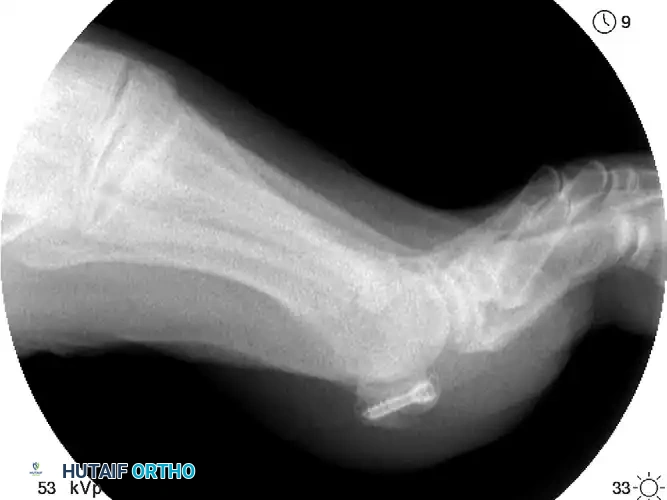

FIGURE 88-80: Mini-fragment screw fixation of a sesamoid fracture, demonstrating precise intra-osseous placement to achieve compression while avoiding the articular surface.